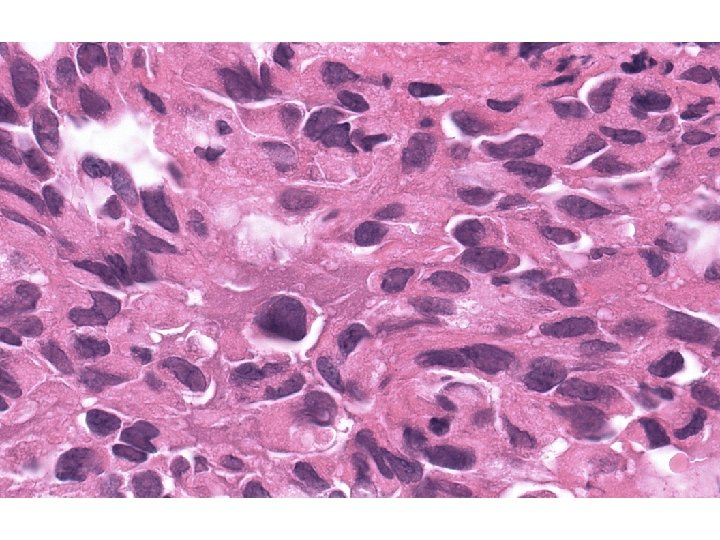

Histopatologický nález • Tumor: ložiskovitě nekrotizující a prokrvácené tumorosní masy tvořené buněčnými skupinami a

Histopatologický nález • Tumor: ložiskovitě nekrotizující a prokrvácené tumorosní masy tvořené buněčnými skupinami a pruhy větších polygonálních až vřetenitých buněk vykazujících cytonukleární polymorfismus i mitotickou aktivitu. • Linea serrata: lymfoplasmocytární zánětlivá infiltrace sliznice subepiteliálně, s úseky úplné intestinální metaplasie epitelu – Barrettův jícen.

? Nízce diferencovaný karcinom? Stromální tumor? Jiný tumor?